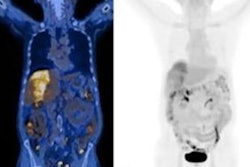

Complete response to immune checkpoint inhibitor therapy on Ga-68 PSMA-PET/CT. Maximum intensity projection (MIP) images from an 83-year-old male with metastatic HCC treated with atezolizumab and bevacizumab. (A) Baseline pretreatment image demonstrates a large, intensely PSMA-avid lesion in the right hepatic lobe, along with multiple metastatic lesions throughout the abdomen and skeleton. (B) Follow-up scan performed four months after initiating therapy shows complete resolution of PSMA uptake in all hepatic and extrahepatic disease.European Journal of Nuclear Medicine and Molecular Imaging